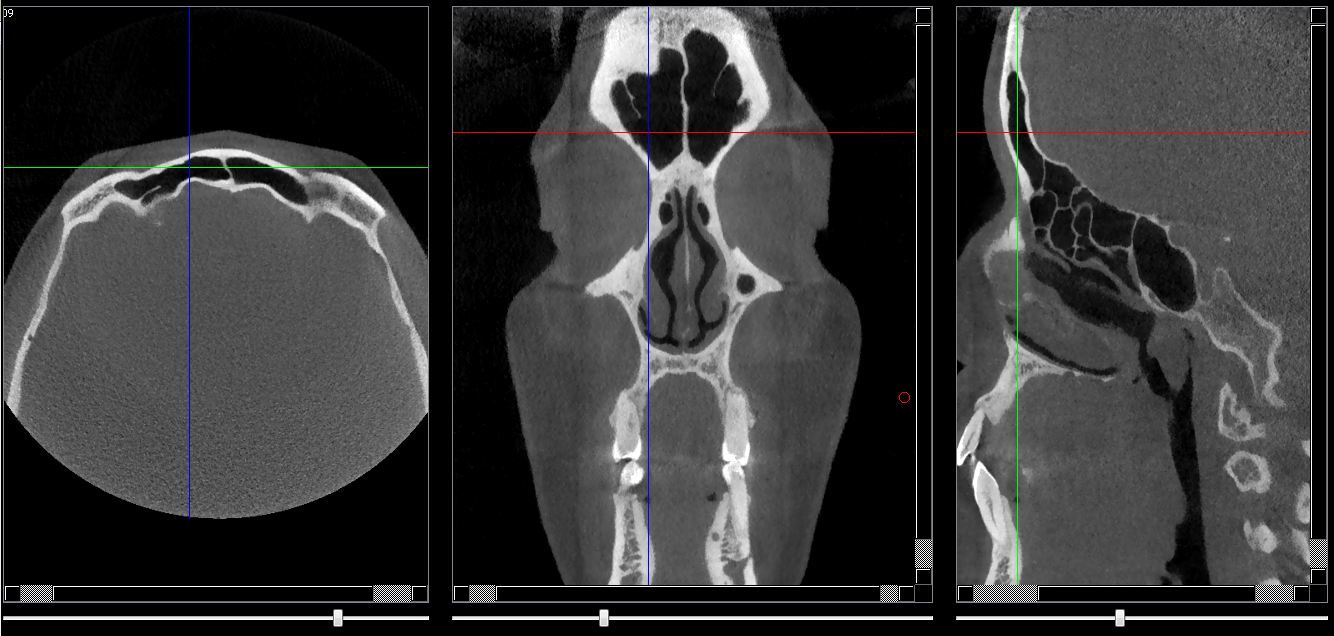

Sinus frontal

Coupe de 1 mm passant par la partie antérieure du sinus frontal